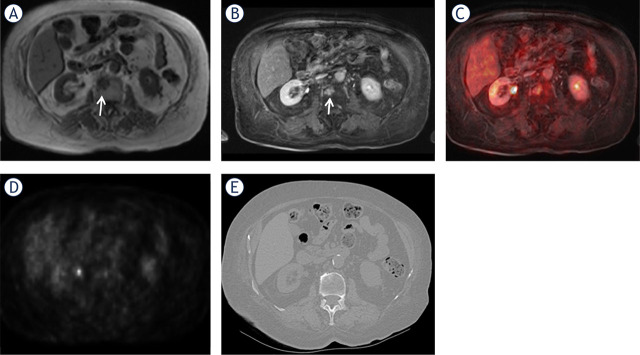

Background: Whole-body positron emission tomography/magnetic resonance imaging (WB-PET/MRI) is increasingly used in the initial evaluation of oncology patients. The purpose of this study was to compare the diagnostic performance of WB MRI sequences, attenuation-corrected raw data positron-emission tomography (AC PET), and PET/MRI fused images to detect bone metastases.

Patients and methods: We included 765 consecutive oncologic patients who received WB-PET/MRI from between January 2017 and September 2023. The presence of bone metastases was assessed using the individual sequences by two radiologists. Interobserver agreement was calculated. A receiver operating characteristic (ROC) analysis was performed to assess the performance of each individual sequence and fused images.

Results: Interobserver agreement for the detection of bone metastases on all sequences ranged from good to very good. The reading of the combination of MRI sequences with PET images showed statistically significantly better performance than the reading of individual MRI sequences and PET component only. Contrast enhanced T1 W Volume-interpolated breath-hold examination (CE T1W VIBE) sequence superior to PET for the detection of bone metastasis, but the statistical significance was not as high as with T1W-PET and CE T1W-PET fused images. The highest performance was achieved by the fused CE T1W-PET images with sensitivity of 100%, specificity of 92%, PPV of 96%, and NPV of 100%.

Conclusions: The combination of these CE T1W VIBE sequences with PET images have the highest diagnostic performance in detecting bone metastases in oncologic patients. This sequence should be integrated in WB-PET/MRI acquisitions for initial staging of cancer.